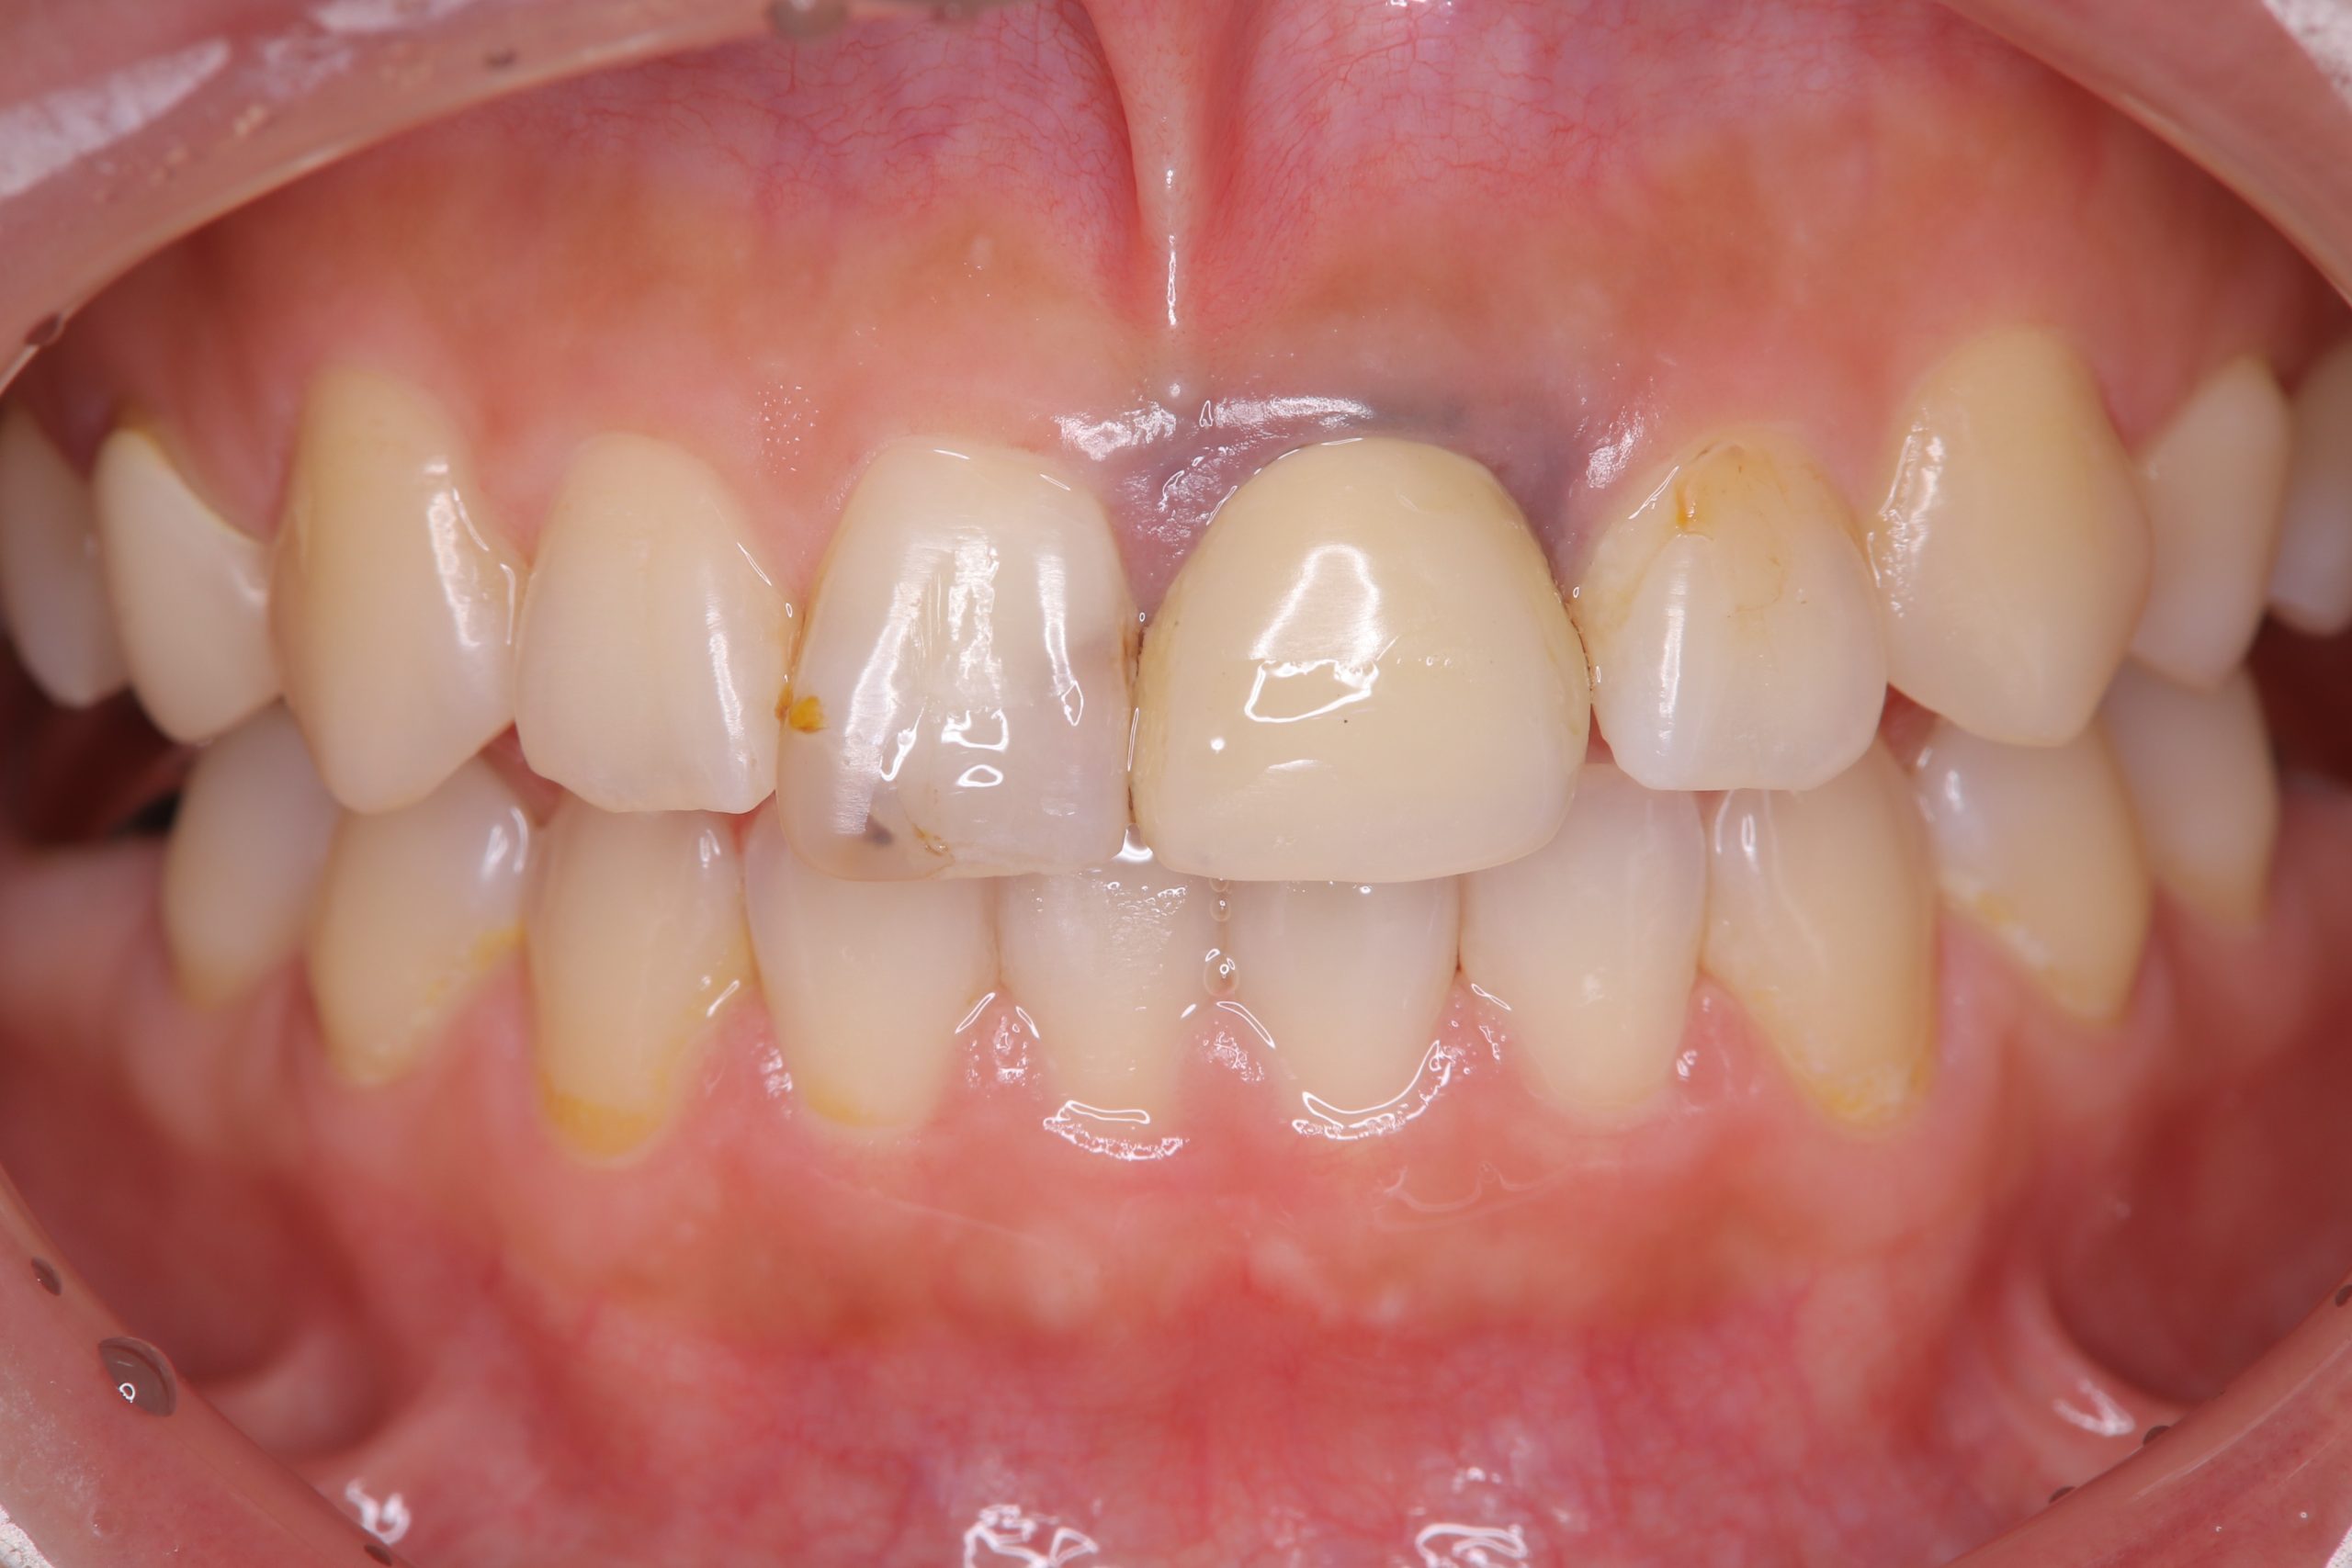

前歯部のメタルタトゥーの相談でいらした患者さんです。

7~8年前に左上中切歯にクラウンを装着したそうですが、歯肉の黒ずみが強く、ずっと気になっていたそうです。

確認すると、歯肉の黒ずみは広範囲にわたっており、クラウンの形が反対側の前歯と大きく違う点も、審美性を損なう原因になっていました。